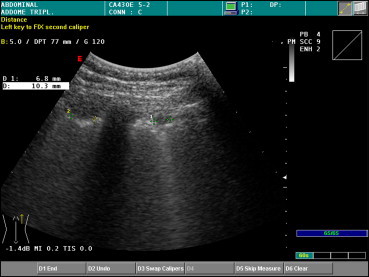

Pulmonary echinococcal cyst with small daughter cysts (Type CE3b in the WHO Classification).